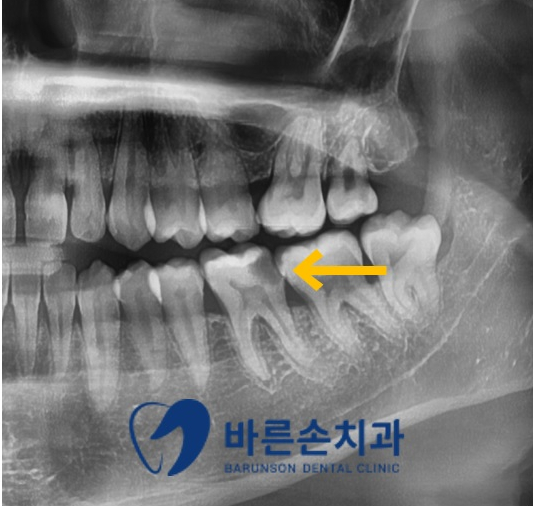

정확한 진단을 위해 파노라마 엑스레이 촬영을 하였습니다

판독 결과 충치와 파절 범위가 신경관에 도달되어 있는 것이 확인되어

신경치료와 크라운 치료를 진행하기로 하였고

염증과 부종이 있던 잇몸을 잇몸치료를 통해 치료하기로 하였습니다!